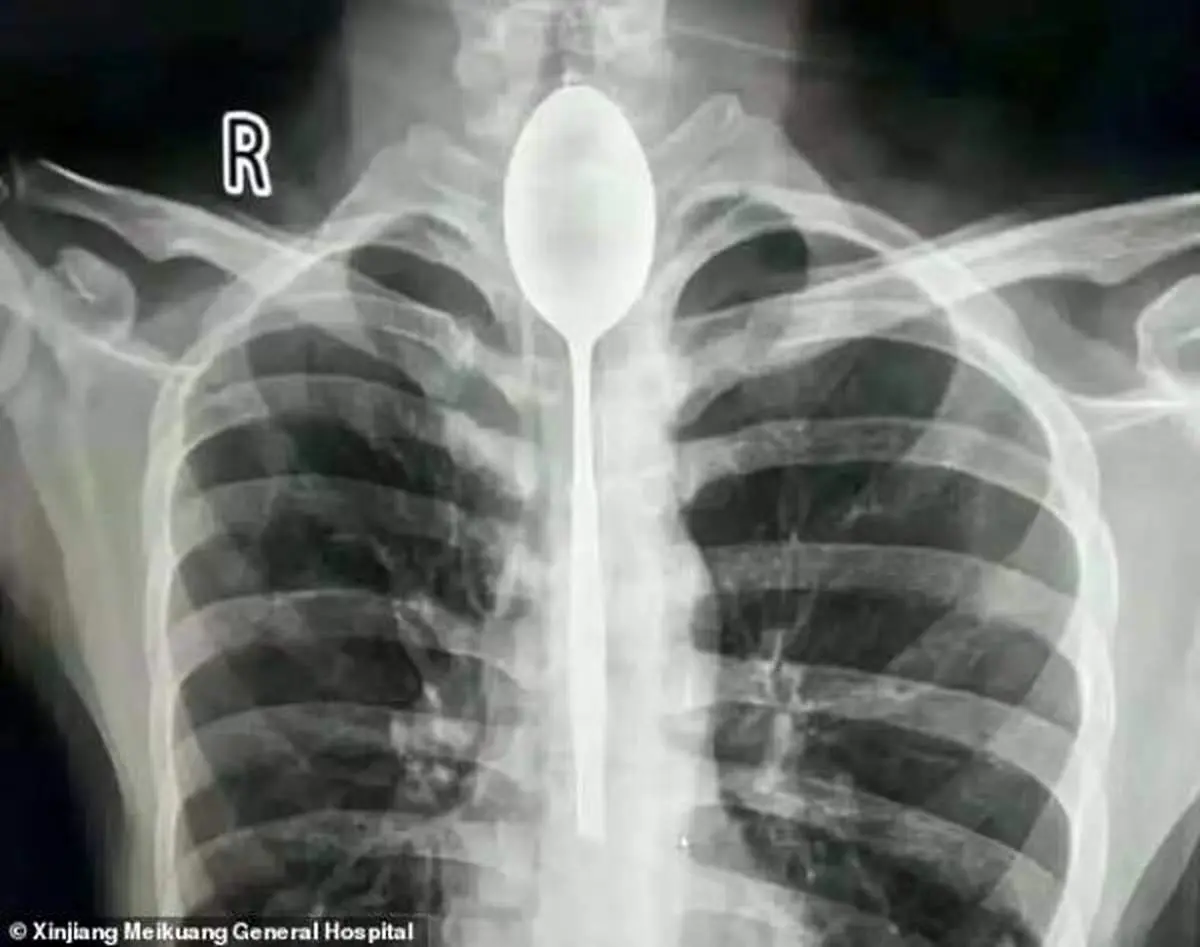

به گزارش منیبان؛ مرد چینی قاشق فلزی 8 اینچی را به عنوان یک شیرین کاری احمقانه در سال گذشته بلعید. قاشق در مری او گیر کرد، اما چون به راحتی می توانست بخورد و بنوشد، هرگز به دنبال کمک پزشکی برای بیرون آوردن آن نبود. او می گوید تنها چند روز پیش به علت ضربه وارد شده به قفسه سینه ، دچار درد قفسه سینه شد.

مردی که نامش فاش نشده است از منطقه جین جیانگ چین به پزشکان گفت :او یک قاشق فولادی ضد زنگ را در طی یک شرط درحالت مستی بلعیده . او به دوستانش گفته که می تواند قاشق را ببلعد و بعد دوباره با ریسمانی که به دسته قاشق می بندد آن را بیرون آورد . در آن زمان برای او حتما فکر خوبی به نظر می رسید، اما همه چیز طبق برنامه پیش نرفت و قاشق در گلوی او گیر کرد. به جای رفتن به بیمارستان، مرد منتظر ماند تا ببیند آیا قاشق به طور عادی از خوردن و نوشیدن جلوگیری می کند یا نه ؛ این طور نبود، پس در مری ماند تا سال گذشته.

قاشق مدت طولانی در سینه او مانده بود و براثر ضربه ای که به سینه او وارد شده بود باعث درد شدید و تنفس بدبو او شده بود . سرانجام به بیمارستان عمومی جین جیانگ رفت و به پزشکان گفت یک سال است که قاشق فلزی در مری او گیر کرده است.

پزشکان در بیمارستان عمومی جین جیانگ پس از بحث در مورد بهترین مسیر عمل تصمیم گرفتند که بهترین راه خارج کردن قاشق ، از طریق دهان بوده است. داروی بی هوشی به بیمار دادند و یک تیم دو ساعت تلاش کردند تا با استفاده از تجهیزات آندوسکوپی ، قاشق 8 اینچی را بیرون آوردند.